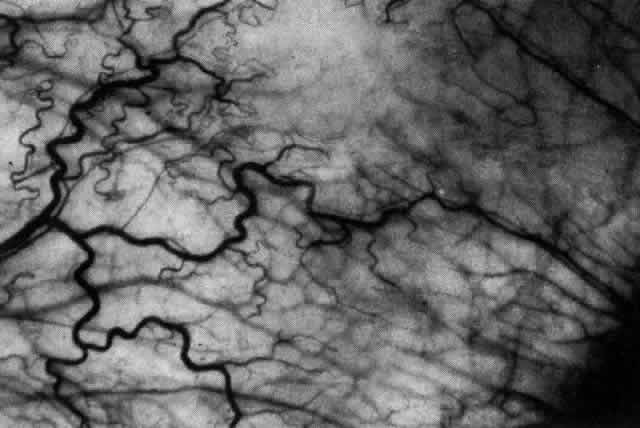

ARTERIAL PHASE Anterior Episcleral Arterial Circle The anterior ciliary arteries run radially toward the limbus within Tenon's capsule, giving few, if any, branches until they reach the anterior part of the globe. Their positions are very variable, and they do not always follow the rectus muscles. They bifurcate 2 to 5 mm behind the limbus, and each division runs forward and circumferentially to anastomose with a branch from an adjacent artery. This results in an anterior episcleral arterial circle (Figs. 3 through 5). The divisions of the anterior ciliary arteries are typically superficial at their origins but run deeper at their anastomoses. They occasionally dip too deep to be seen in fluorescein angiograms (Fig. 6).

From the anterior episcleral arterial circle, four distinct circulations are supplied: episcleral, anterior conjunctival, limbal, and iris. Episcleral Circulation Immediately after their origin by bifurcation of the anterior ciliary arteries, the contributions to the anterior episcleral circle divide again to give recurrent branches that run posteriorly and subdivide to form a netlike episcleral plexus (see Fig. 5; Fig.7). The variability of the positioning of the anterior ciliary arteries inevitably leaves large areas of episclera far from such an arterial supply (see Figs. 4, 6, and 7). These areas receive other posterior branches from the episcleral circle. Where the circle runs deep within the sclera, such branches appear as isolated perforating vessels (see Fig. 6). They fill very shortly after the episcleral circle, and they also divide repeatedly as they run posteriorly.

Anterior Conjunctival Circulation Throughout their superficial course, the arteries of the episcleral circle give off fine loops that run forward into the limbal reflection of the conjunctiva before curving back radially and dividing to form the lacework of the anterior conjunctival capillary plexus (see Fig. 2). The delicate column of blood within the anterior conjunctival loops may be punctuated by a string of individual erythrocytes, suggesting that the lumen is approximately 12 μm in diameter. Anterior conjunctival loops may also arise from perforating posterior branches of the episcleral circle (see Fig. 6). The anterior conjunctival circulation, supplied by the anterior ciliary arteries, always fills before the posterior conjunctival circulation, which is derived from the posterior tarsal vessels (see Figs. 4 and 5). The watershed zone between these sources can fill very late (see Fig. 5). However, anterior conjunctival loops do sometimes anastomose with arteries of similar caliber derived from the posterior tarsal circulation. Limbal Arcades Limbal arcades are supplied by anterior branches from the episcleral circle. Their origins are often shared with those of the anterior conjunctival loops, and, where the circle runs deep, they too are derived from the perforating posterior branches. They often fill very late during a normal angiogram (see Fig. 7). The limbal capillary loops never leak fluorescein, even during high-dose angiograms, suggesting that their endothelial cells are united by tight junctions. Iris Vessels The first flush of fluorescein within the anterior episcleral arterial circle always coincides with filling of the radial arterioles of the iris. It may be implied from this that the iris receives a major supply from the anterior ciliary circulation (see Fig. 6). In some angiograms, the iris circulation appears to derive directly from the episcleral circle. This raises the possibility that the “major circle of the iris” and the episcleral arterial circle are less distinct entities than has hitherto been presumed. VENOUS PHASE Anterior ciliary veins accompany the arteries, but there is no well-organized venous ring corresponding to the anterior episcleral arterial circle. The posterior episcleral branches of the arterial circle are paralleled by centripetal venules, and looping anterior conjunctival venules are interspersed between the arterioles (see Figs. 4 and 5). The posterior conjunctiva drains back into the tarsal circulation. CAPILLARY PHASE The episcleral capillary net is often difficult to discern below the more prominent conjunctival circulation. It is most clearly seen when the conjunctival circulation fills late for anatomic or pathologic reasons. The anterior conjunctival capillary plexus forms an interlacing network between the anterior conjunctival arterioles. Perfusion of the watershed zone that separates the territories supplied by the anterior ciliary and posterior tarsal systems may be delayed by as much as 15 seconds after first flush (see Figs. 5 and 7). However, this region is often crossed by arteriolar anastomoses between the two circulations, and the destination of venous blood is irrespective of its origin from the anterior ciliary or posterior tarsal circulations. |